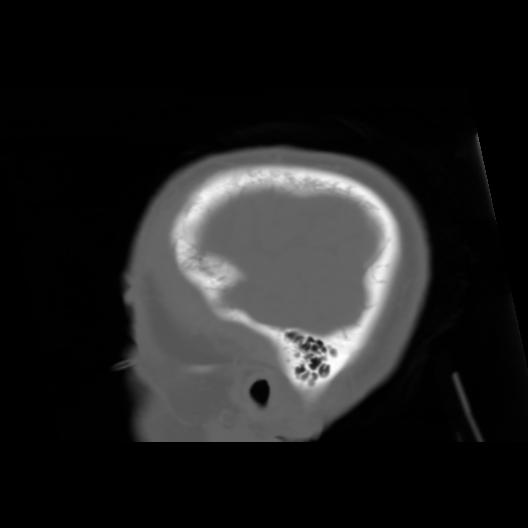

6 CEREBRO,,Sagittal,3.000,CEREBRO,Sagittal,